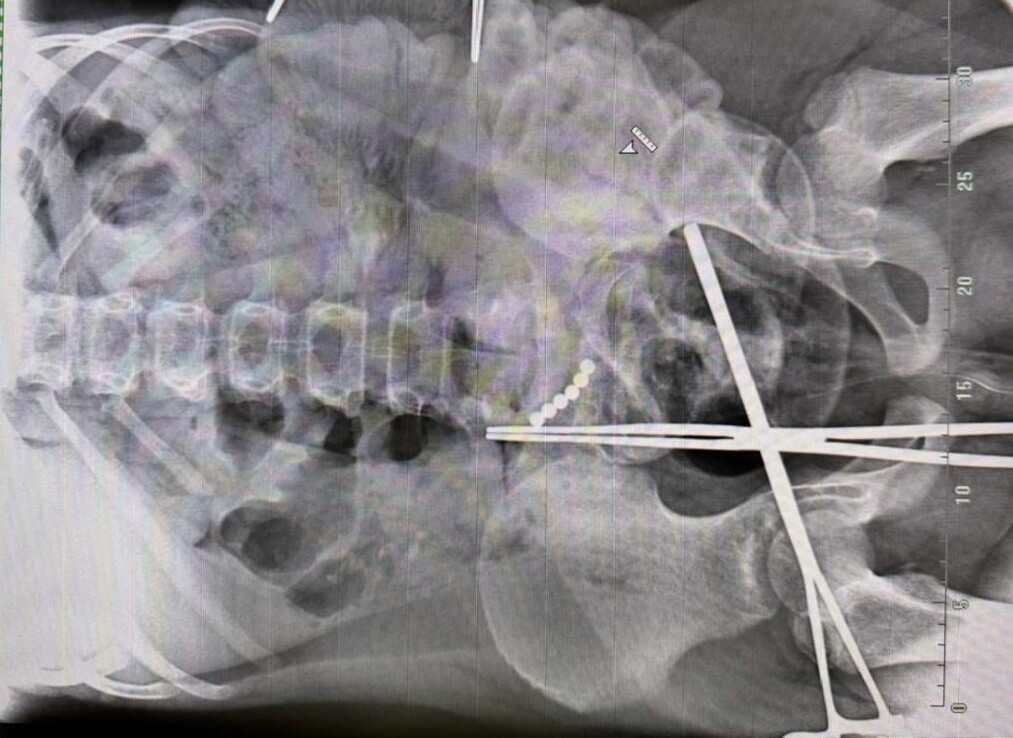

Экстренную операцию провели для 10-летнего мальчика, который проглотил 19 магнитных шариков. Об этом рассказали в областной детской клинической больнице.

Ребёнок проходил с опасными предметами в животе целый месяц, пока не развился перитонит. После этого попал в реанимацию. Хирурги обнаружили множество межкишечных свищей, их разобщили и ушили. Кроме того, начинали операцию с помощью прокола, однако позже пришлось перейти на лапаротомию — открытое вмешательство, когда делается разрез.

— Важно понимать: операции такого рода проходят успешно, но почти всегда остаются последствия. Разные. Возможна спаечная болезнь, при которой приходится выполнять релапаротомию, — уточнил хирург Сергей Кузнецов.